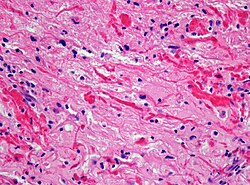

| Glioblastoma (WHO grade IV) | glial processes (esp. on smear), nuclear atypia (typical size var. ~3x, irreg. nuc. membrane, hyperchromasia), no Rosenthal fibres in the core of the lesion †, microvascular proliferation or necrosis | often enhancing (suggests high grade), usu. supratentorial, usu. white matter | usu. old, occ. young | very common, esp. glioblastoma | IDH-1+/-, GFAP+ | |

- Endothelial proliferation in a GBM (ouhsc.edu).

- Endothelial proliferation (ouhse.edu).

Images

Glioblastoma: